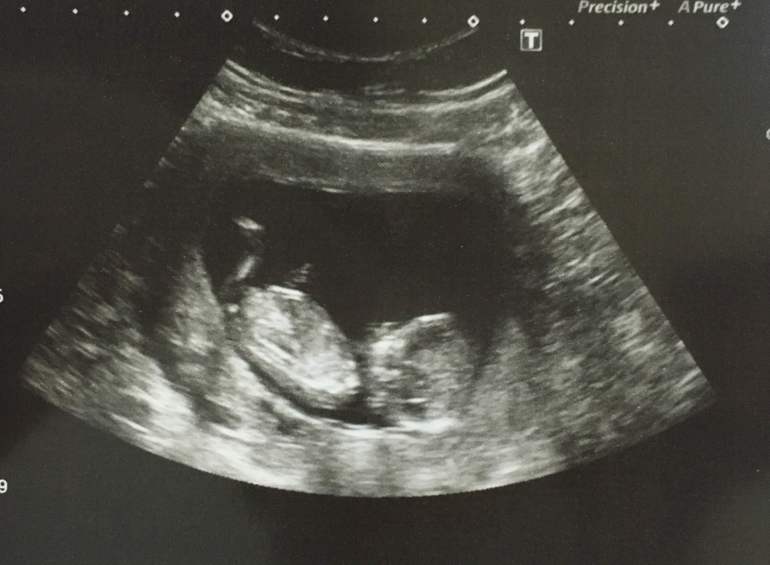

И вот наше фото . Кто-нибудь умеет определять пол по фото так рано ? Мне кажется там не плохо видно достоинство , в Великобритании к сожалению ранее 20 недели они ничего не говорят, поэтому промолчали .